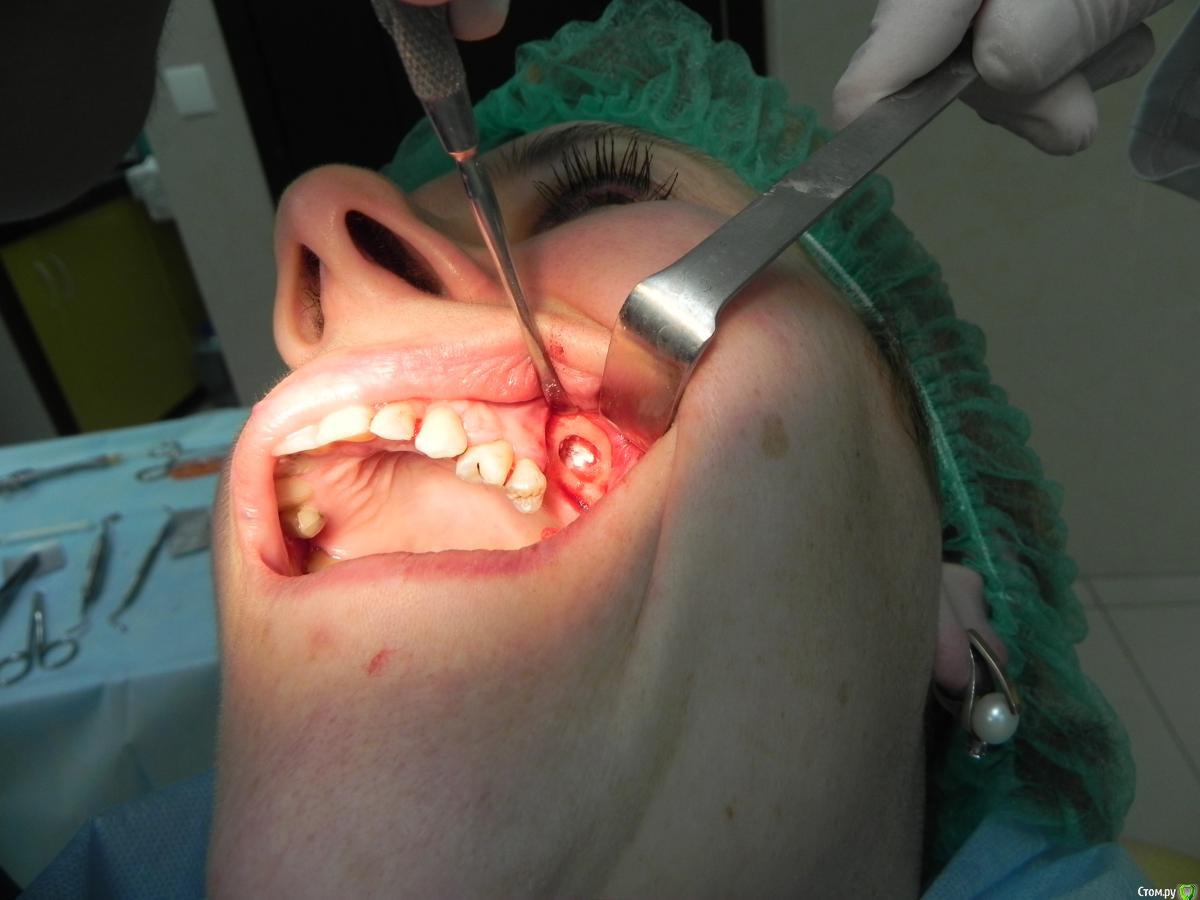

Kostoprav Опубликовано 7 августа, 2015 Поделиться Опубликовано 7 августа, 2015 доступпрепаровка шаровидной костной фрезойпри отслаивании мембраны образовалась маленькая перфа перфорацию" проклеил" коллагеновой мембранойпод мембрану внесен материалмембрана на окноготово может кому из начинающих этот пост полезен будет 1 Ссылка на комментарий

Bier Опубликовано 8 августа, 2015 Поделиться Опубликовано 8 августа, 2015 Коллега, режьте фотки. Кадрируйте т.е есть много очень простых редакторов для этого. А так все прилично, но я бы не стал так близко от костного окна располагать разрезы 3 Ссылка на комментарий

DoctorN Опубликовано 8 августа, 2015 Поделиться Опубликовано 8 августа, 2015 если при синус-лифтинге продлить внутрисосочковый разрез на пару зубов-вертикальный либо совсем не понадобится,либо он будет проходить на удалении от края мембраны. при расхождении швов не так страшно 1 Ссылка на комментарий